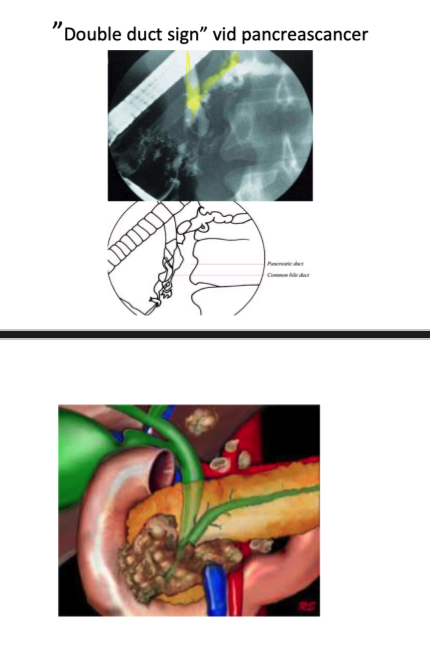

1. Vad är double duct sign för något som kan ses vid ERCP med genomlysning och vilken diagnos tyder detta på?

1. Double duct sign = pankreasgången är lika vid typ som gallgången (inte normalt). Detta beror på stas i gallgången som orsakas av en obstruerande pankreascancer.

2. Man kan stenta med plast eller metallstent, vid papilla vateri t.ex.